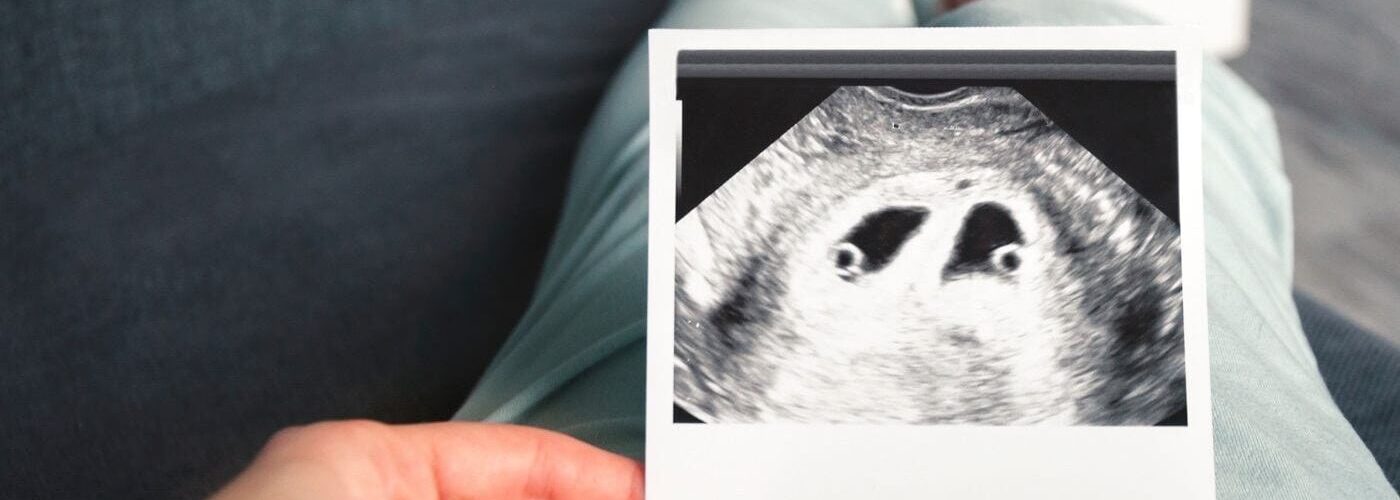

Embarazo múltiple con FIV: ¿gemelos o mellizos?

Cuando hablamos de embarazo múltiple tras una FIV, los recién nacidos serían mellizos, no gemelos idénticos. Esto se debe a que proceden de 2 embriones distintos. Los gemelos surgen cuando un único ovocito fecundado se divide en dos, dando lugar a dos embriones idénticos.